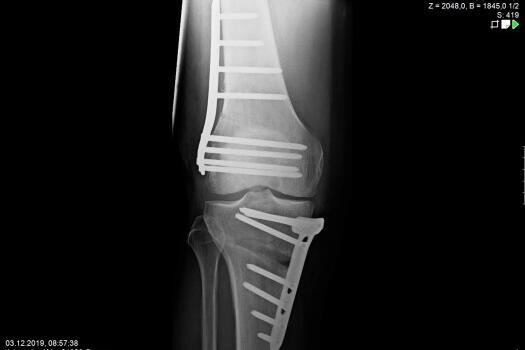

Pathological deformities of the upper or lower leg bones result in incorrect loads on the knee joint, but they can also result in restricted movement. A precise axis analysis, which we can perform with the help of a computer programme, shows us the location of the deformity. This enables us to carry out a correction at the site of the malposition by cutting through the bone (osteotomy) and then stabilise this correction with stable-angle plates. Partial weight-bearing and free mobility is usually possible immediately. Osteotomies close to the knee joint on the upper leg (femur) and lower leg (tibia) have proven successful in the prevention and treatment of osteoarthritis and in the treatment of ligament instabilities.